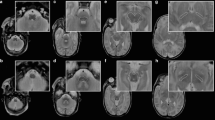

To analyse the DTI, the regions of interest (ROIs) were manually drawn in apparent diffusion coefficient maps and FA in the same voxels in which metabolites were measured, using an automatic correlation of the slices in the dedicated picture archiving and communication system Impax EE (Agfa Healthcare) (Fig. 2). The mean numbers and SD values for MD and FA were considered for further evaluation. FA is a unitless measure; MD has a unit of 10−3 mm2/s.

Regions of interest (ROIs) in all regions evaluated, positioned in MD (a), FA (b) and MRS localiser (c). Corresponding spectrum in frontal white matter on the right side (d). Frontal white matter right (FWMR) and left (FWML) in blue, central white matter right (CWMR) and left (CWML) in green and parietal white matter right (PWMR) and left (PWML) in orange